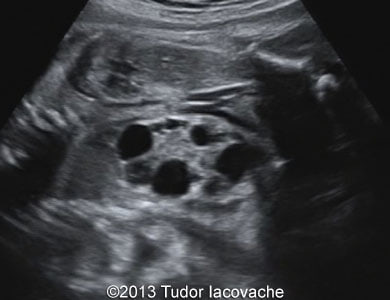

The patient was a 28-year-old primigravida. Fetal hydronephrosis with dilated renal pelvis and calices of the left kidney was noticed at 17 weeks. At 23 weeks the left kidney showed signs of multicystic dysplasia - the enlarged kidney consisted of isolated multiple cysts of various sizes. At 29 weeks the finding was even more striking. The right kidney was normal throughout the pregnancy. The multicystic dysplastic kidney was confirmed after birth.

Images 1, 2, and video 1: 17 weeks of gestation.